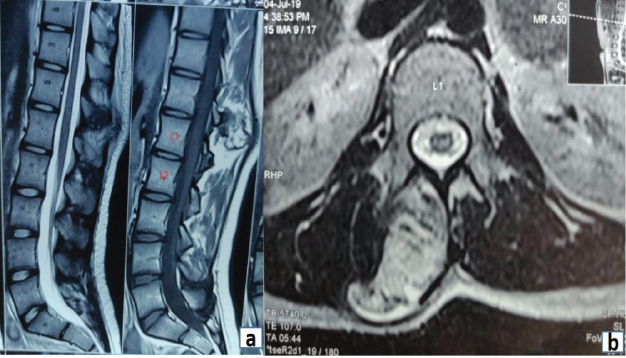

Neurological examination was normal. Computed tomography (CT) scan showed a pedunculated bony outgrowth arising from the right pedicle of L1 vertebral body projecting postero-superiorly, with a fracture at the base (Fig. 2a, b and c). MRI done also showed similar findings and an overlying cartilaginous cap of 2.3 mm thickness. The bony central spinal canal dimensions were normal with no evidence of primary canal stenosis (Fig. 3a and b). Under general anesthesia, an excision biopsy of the tumor mass was done through a posterior approach. Histopathological examination of the specimen as showed in Fig. 4. Postoperatively, the patient was symptomatically better, and on subsequent follow-ups did not show any recurrence or pain.

Figure 3: (a and b) Magnetic resonance images as described.